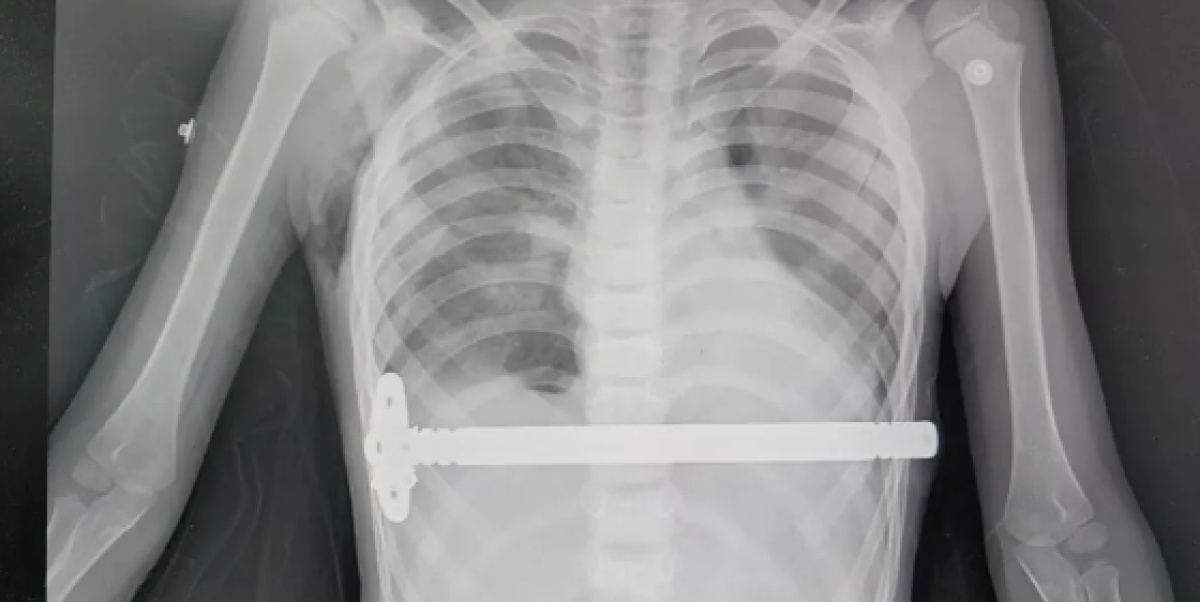

手术在患者全麻下进行,侯智亮从孩子两侧胸壁分别做好的一个约1厘米的小切口处,将一枚根据孩子胸廓弧度预先塑形的矫形钢板,小心翼翼地穿过胸骨后,翻转180度,将凹陷处挺举起来,恢复到正常位置。

手术过程非常顺利,仅用时40分钟,出血量约5毫升。术后,孩子清醒后拔除气管插管,安全返回病房。

这次手术采用的是胸腔镜辅助微创胸骨凹陷(漏斗胸)矫治术,也就是常说的Nuss手术,是目前治疗漏斗胸的主流微创方式,也是胸外科五病区的常规开展项目。依托河南省胸科医院在心胸疾病领域的专科优势,胸外五病区侯智亮医师团队十余年来深耕复杂胸廓畸形矫正领域,积累了1200余例临床经验,致力于为每一位患者提供精准微创、快速康复的个体化诊疗方案。